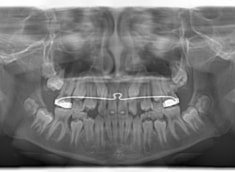

治療法:上顎急速拡大装置+クリアスナップ+フェイスマスク+上顎3番は開窓牽引CT写真にて位置確認

検査時のレントゲン分析では、上下顎の関係は、上顎の劣成長があり下顎前突傾向という値がでておりましたが、前歯ジャンプ後はフェイスマスクの効果もあり、上下顎の関係は正常化しています。

上顎が若干優位になっていますので、今後の下顎の成長のための貯金になっているくらいです。